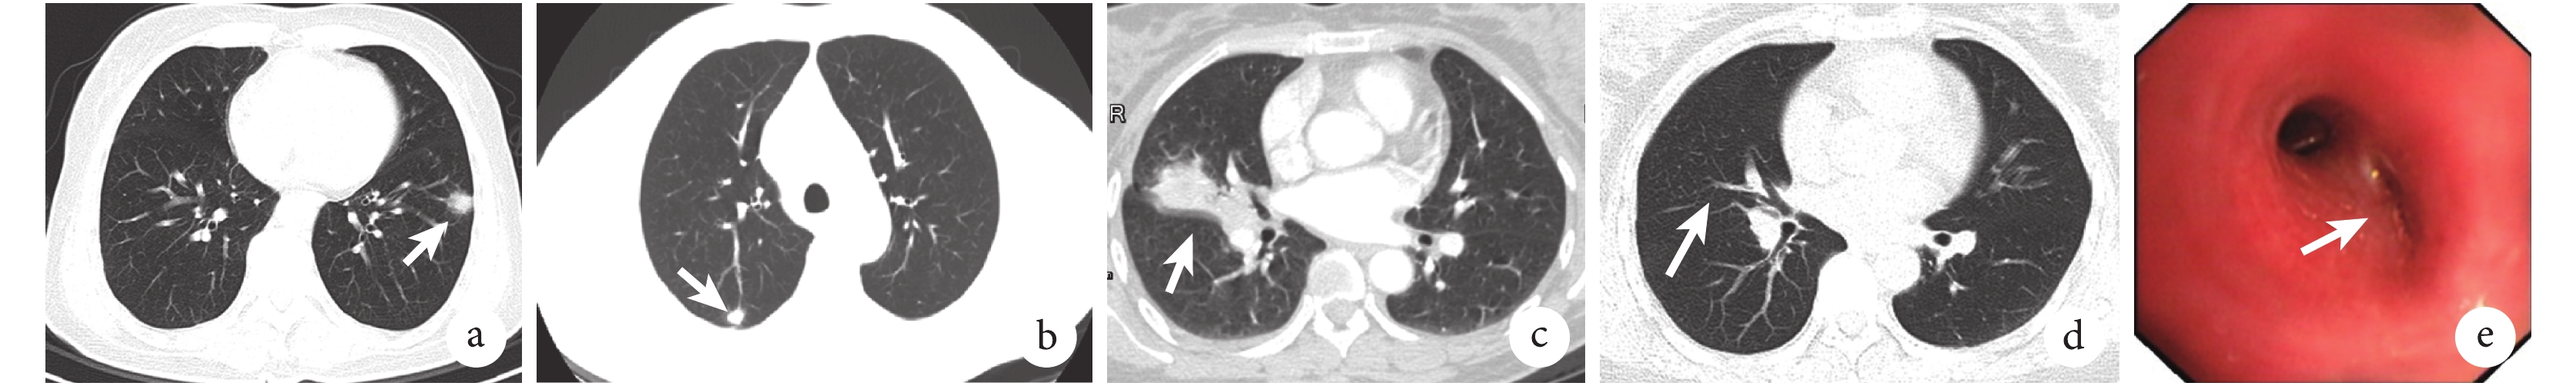

72 例(包括支氣管隱球菌病 1 例)肺隱球菌病患者中,男 39 例,女 33 例,年齡 23~69 歲,平均年齡 48.4 歲。其中,無癥狀體檢發現者 40 例,咳嗽 32 例,咳痰 21 例,氣喘 8 例,痰中帶血 8 例,發熱 23 例,體溫在 37.3~38.5 ℃。26 例白細胞計數升高,中位數為 8.85×109/L;降鈣素原升高 17 例,中位數為 0.13 μg/L。72 例中 66 例的病灶位于肺野外周帶;雙肺均有病灶者 37 例,以下肺部受累多見;單發性結節影 21 例,多發結節影 32 例,其中右肺 21 例,左肺 14 例;多發斑片狀影 8 例,腫塊伴多發結節 15 例,彌漫性肺實質浸潤影 7 例;病灶內可見空洞或空泡征 9 例,伴縱隔淋巴結腫大 7 例;胸腔積液 6 例。部分典型患者的影像檢查及支氣管鏡檢查結果見圖 2。

a. 患者男性,40 歲,反復咳嗽 2 個月,肺部 CT 示左下肺周邊靠胸膜結節影(白箭);b. 患者女性,43 歲,體檢時行肺部 CT 發現右上肺后段周邊靠胸膜結節影(白箭);c. 患者女性,46 歲,咳嗽、咳痰、咯血 20+d,肺部 CT 示右肺中葉不張(白箭);d. c 圖同一患者治療后 7 個月復查肺部 CT 示右中葉復張(白箭);e. c 圖同一患者支氣管鏡下見右中葉外側段支氣管管腔狹窄(白箭)

本研究中有經病理確診肺隱球菌病而血清 CrAg-LFA 抗原結果呈陰性者 18 例,其中 13 例 BALF CrAg-LFA 抗原結果呈陽性;部分病例無臨床癥狀而是肺 CT 體檢發現位于肺邊緣甚至靠近胸膜的小病灶(圖 2 的 a、b 小圖)。有文獻指出,CrAg 檢測的假陰性多出現于感染早期[14-15]。本研究中 BALF CrAg-LFA 陽性率及敏感性高于血清的現象,我們推測與隱球菌在肺部浸潤性生長,CrAg 較難或早期尚未或較少釋放入血有關,尤其是小病灶或無全身癥狀患者,此外有報道可能也與肺部病變局部隱球菌載量較高有關[16];此推測有待進一步研究證實。本研究有 5 例確診病例血清及 BALF CrAg-LFA 檢測結果同時呈陰性,多為微小病灶、無癥狀的患者,提示此種情況 BALF CrAg-LFA 也可能存在假陰性的結果,值得臨床重視。本組有 1 例典型的支氣管隱球菌確診病例,其病變位于右中葉外側段支氣管(圖 2 的 c~e 小圖),血清及 BALF CrAg-LFA 結果呈陰性,而支氣管沖洗液 CrAg-LFA 結果呈陽性,此結果提示只有病變組織的沖洗液才能早期獲得陽性結果。本研究未發現有確診病例血清 CrAg-LFA 抗原陽性而 BALF 呈陰性的檢測結果。